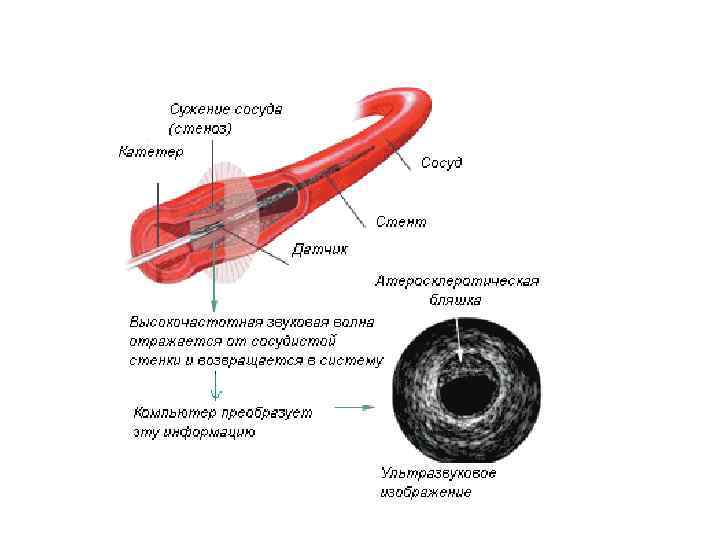

Внутрисосудистый ультразвук • исследование артерий (например, коронарных) с использованием специального внутрисосудистого датчика малого диаметра. • Инвазивный ультразвуковой метод. • Используется параллельно с коронарографией.

Внутрисосудистый ультразвук • исследование артерий (например, коронарных) с использованием специального внутрисосудистого датчика малого диаметра. • Инвазивный ультразвуковой метод. • Используется параллельно с коронарографией.

Внутрисосудистое ультразвуковое исследование (ВСУЗИ) • В то время, как ангиография остается золотым стандартом в исследовании коронарных артерий, становится все более и более важным • определение структурных изменений стенки артерии, • а не только степени сужения ее просвета.

Внутрисосудистое ультразвуковое исследование (ВСУЗИ) • В то время, как ангиография остается золотым стандартом в исследовании коронарных артерий, становится все более и более важным • определение структурных изменений стенки артерии, • а не только степени сужения ее просвета.

Коронарограмма пациента с ИБС • а - окклюзия ПМЖВ (стрелка). • б - операция реканализации и стентирование ПМЖВ (стрелка) с полным восстановлением кровотока по этому сосуду. • в - просвет сосуда определяется с помощью внутрисосудистого ультразвука.

Коронарограмма пациента с ИБС • а - окклюзия ПМЖВ (стрелка). • б - операция реканализации и стентирование ПМЖВ (стрелка) с полным восстановлением кровотока по этому сосуду. • в - просвет сосуда определяется с помощью внутрисосудистого ультразвука.